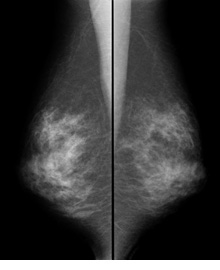

乳がん検診の方法には「視触診」「乳腺エコー(超音波検査)」「乳房撮影(マンモグラフィ)」の3つがあります。視触診と画像診断を組み合せることになります。また、乳腺が発達している方にはマンモグラフィより乳腺エコーの方が検診の精度は高いといわれています。このように個々に合った検診方法を選択する事が大切になります。乳腺エコーはケイアイクリニック(四谷)にて検査を受けることができます。

マンモグラフィはX線検査なので放射線被ばくがありますが、被ばくの線量はほとんど問題のない量といえます。また乳房だけにX線を照射して撮影しますので、他の臓器への影響もほとんどありません。撮影1回あたりの被ばく量は、東京からニューヨークへ飛行機で行くときに浴びる自然放射線とほぼ同じ量だと言われています。

非常に被ばく線量が少なく、鮮明な画像を撮影できるマンモグラフィ装置です